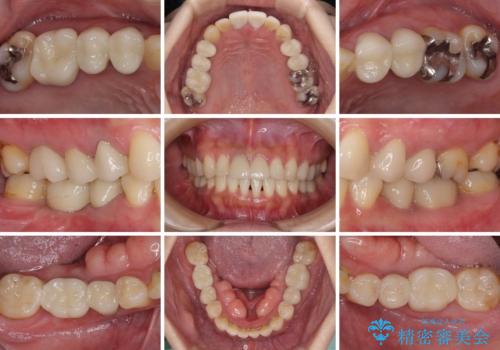

- 右下の欠損部の治療を希望して来院された患者様です。

部分矯正を行った後にインプラント埋入と手前の歯の根管治療を行い、その後補綴治療を行うこととしました。

治療途中より、上の歯や反対側の銀歯、上顎前歯の色合いや下顎前歯のデコボコが気になってきたため、全てを治療することとしました。